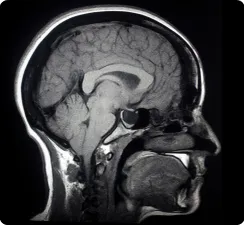

The medical system expects you to chase 33 different screening appointments across multiple specialists and check your organs one at a time. But there’s a smarter way that scans your entire body in under an hour to catch cancer, aneurysms, fatty liver, and other serious health issues before they become life-threatening.

In today’s episode, I sit down with Dr. Daniel Durand, Chief Medical Officer of Prenuvo, to talk about the real-world power (and limitations) of proactive whole-body MRI screening.

Dr. Durand walks us through how this advanced screening method detects over 500 conditions, many of which traditional screenings miss. We talk about the importance of early detection for cancers and neurodegenerative diseases, and how this proactive approach to health can save lives.

The world’s largest network of clinics dedicated exclusively to proactive, radiation-free whole-body MRI screening. Detects hundreds of conditions, including early cancers, aneurysms, and organ abnormalities, in a single comfortable visit.